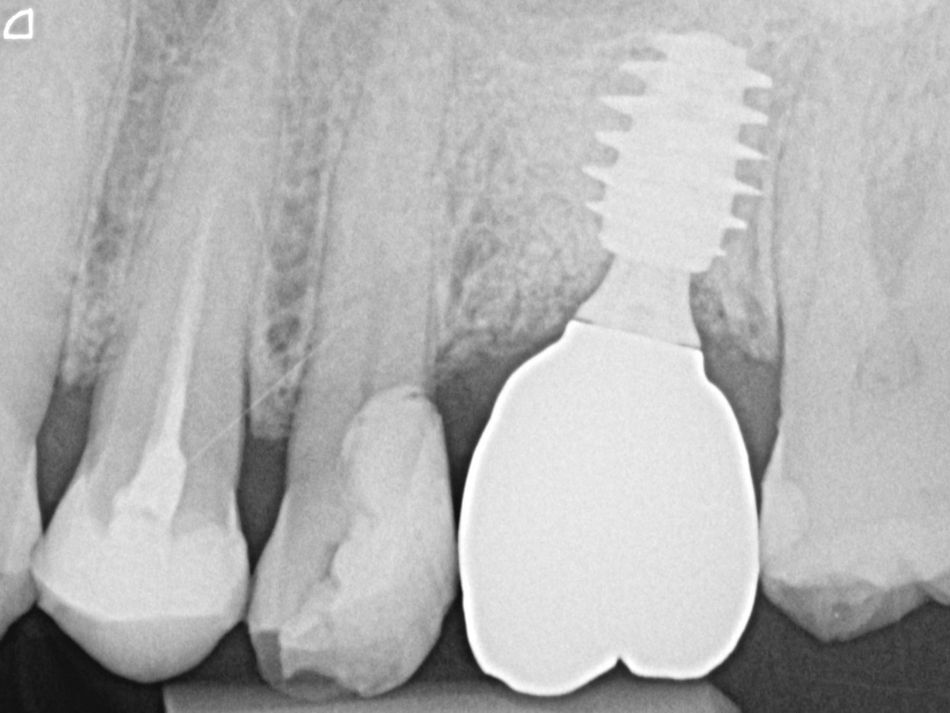

1. Radiograph of initial situation.

1

4. Radiograph exhibiting a suitable septum for immediate implant placement.

4